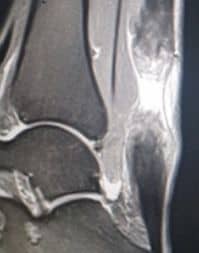

ΠΑΘΗΣΕΙΣ ΠΟΔΟΚΝΗΜΙΚΗΣ & ΑΚΡΟΥ ΠΟΔΟΣ

Διαβάστε περισσότερα για τις παθήσεις ποδοκνημικής και άκρου ποδός